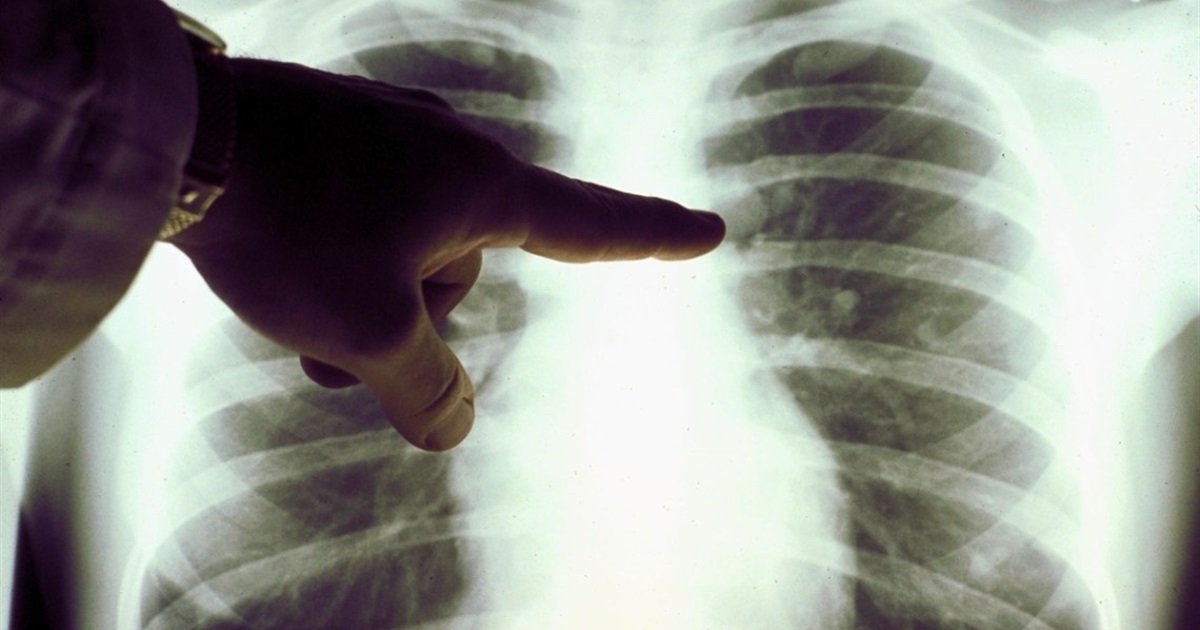

Діагностувати пневмонію допомагають рентгенографія грудної клітки, комп’ютерна томографія, пульсоксиметрія, аналіз крові та мокротиння у сукупності з клінічними ознаками.